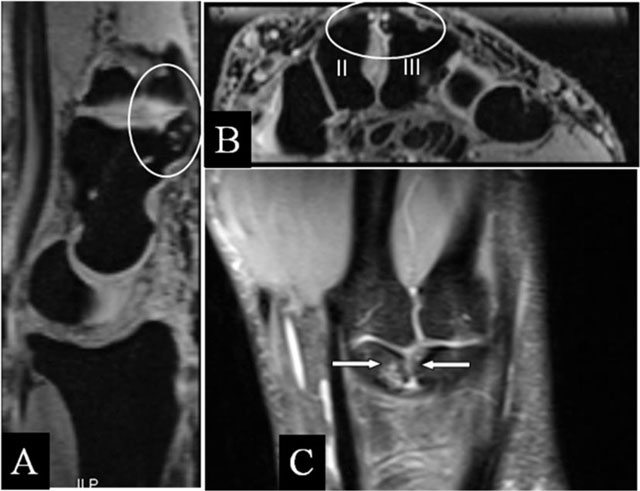

Carpal boss with abutment

Quadrangular joint traumata may result in bony carpal boss [19]. Although the restricted motion, deformations induce juxtaarticular changes (Figure 10A–C). Due to superposition, radiographs are less useful and MRI may help to solve the clinical problem.

Figure 10

Carpal boss with abutment. (A) Sagittal 3D-GRE; (B) Coronal 3D-GRE; and (C) Coronal SE PD-WI FS. (A, B) Old posttraumatic deformation with subchondral cysts at the dorsum of the capitate bone (A) and the base of the second and third metacarpal bone (B) with misalignment around the quadrangular joint. (C) Juxta-articular kissing bone marrow oedema.